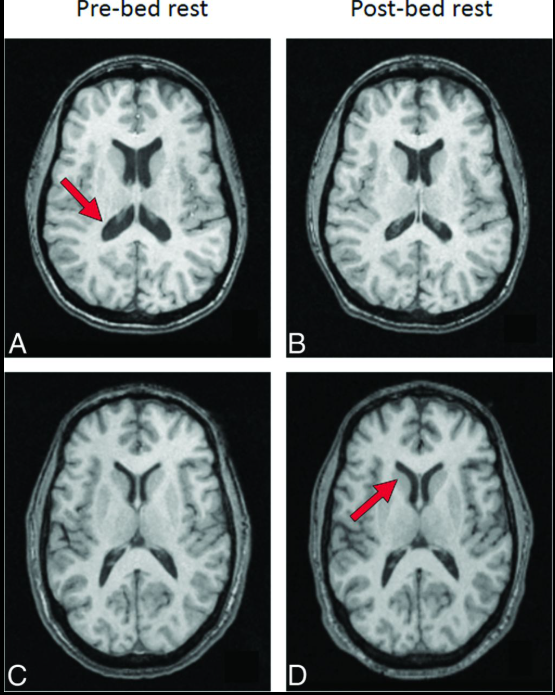

Trong nghiên cứu đăng trên tạp chí Proceedings of the National Academy of Sciences, các nhà khoa học đã công bố loạt ảnh chụp cộng hưởng từ (MRI) não của 26 phi hành gia, được thực hiện trước và sau các sứ mệnh ngoài Trái Đất. Khi đặt các hình ảnh này cạnh nhau, sự khác biệt trở nên rõ ràng.

Não bộ của phi hành gia có xu hướng dịch chuyển lên phía trên và ra sau bên trong hộp sọ. (Ảnh: PNAS)

Theo đó, sau thời gian sống và làm việc trên Trạm Không gian Quốc tế (ISS), não bộ của phi hành gia có xu hướng dịch chuyển lên phía trên và ra sau bên trong hộp sọ. Các rãnh não ở vùng đỉnh đầu bị nén lại, trong khi hệ thống khoang chứa dịch não tủy xuất hiện sự thay đổi về hình dạng.

Đáng chú ý, những biến đổi này không đồng đều trên toàn bộ não bộ. Ảnh MRI cho thấy các vùng liên quan đến cảm giác và vận động – những khu vực đóng vai trò quan trọng trong việc giữ thăng bằng và phối hợp cơ thể là nơi chịu ảnh hưởng rõ rệt nhất. Ngoài ra, các nhà khoa học còn ghi nhận những biến dạng cục bộ theo chiều ngang, mang tính phi tuyến và khác nhau giữa phần trên và phần dưới của não.

Để có cái nhìn toàn diện, nhóm nghiên cứu đã so sánh ảnh MRI của các phi hành gia với 24 người khỏe mạnh trên Trái Đất. Nhóm đối chứng này được đặt trong tư thế nằm nghiêng đầu xuống đất trong thời gian dài, một phương pháp thường dùng để mô phỏng môi trường vi trọng lực.

Kết quả cho thấy não bộ của nhóm người này cũng xuất hiện sự thay đổi về hình dạng và vị trí, khá giống với những gì quan sát được ở phi hành gia. Tuy nhiên, mức độ dịch chuyển lên trên của não không mạnh bằng, và các cấu trúc não nhìn chung vẫn ổn định hơn so với những người thực sự sống trong không gian.

Não bộ của người thường được đặt trong mô phỏng môi trường vi trọng lực mức độ dịch chuyển lên trên của não không mạnh bằng, và các cấu trúc não nhìn chung vẫn ổn định hơn so với những người thực sự sống trong không gian. (Ảnh: AJNR)